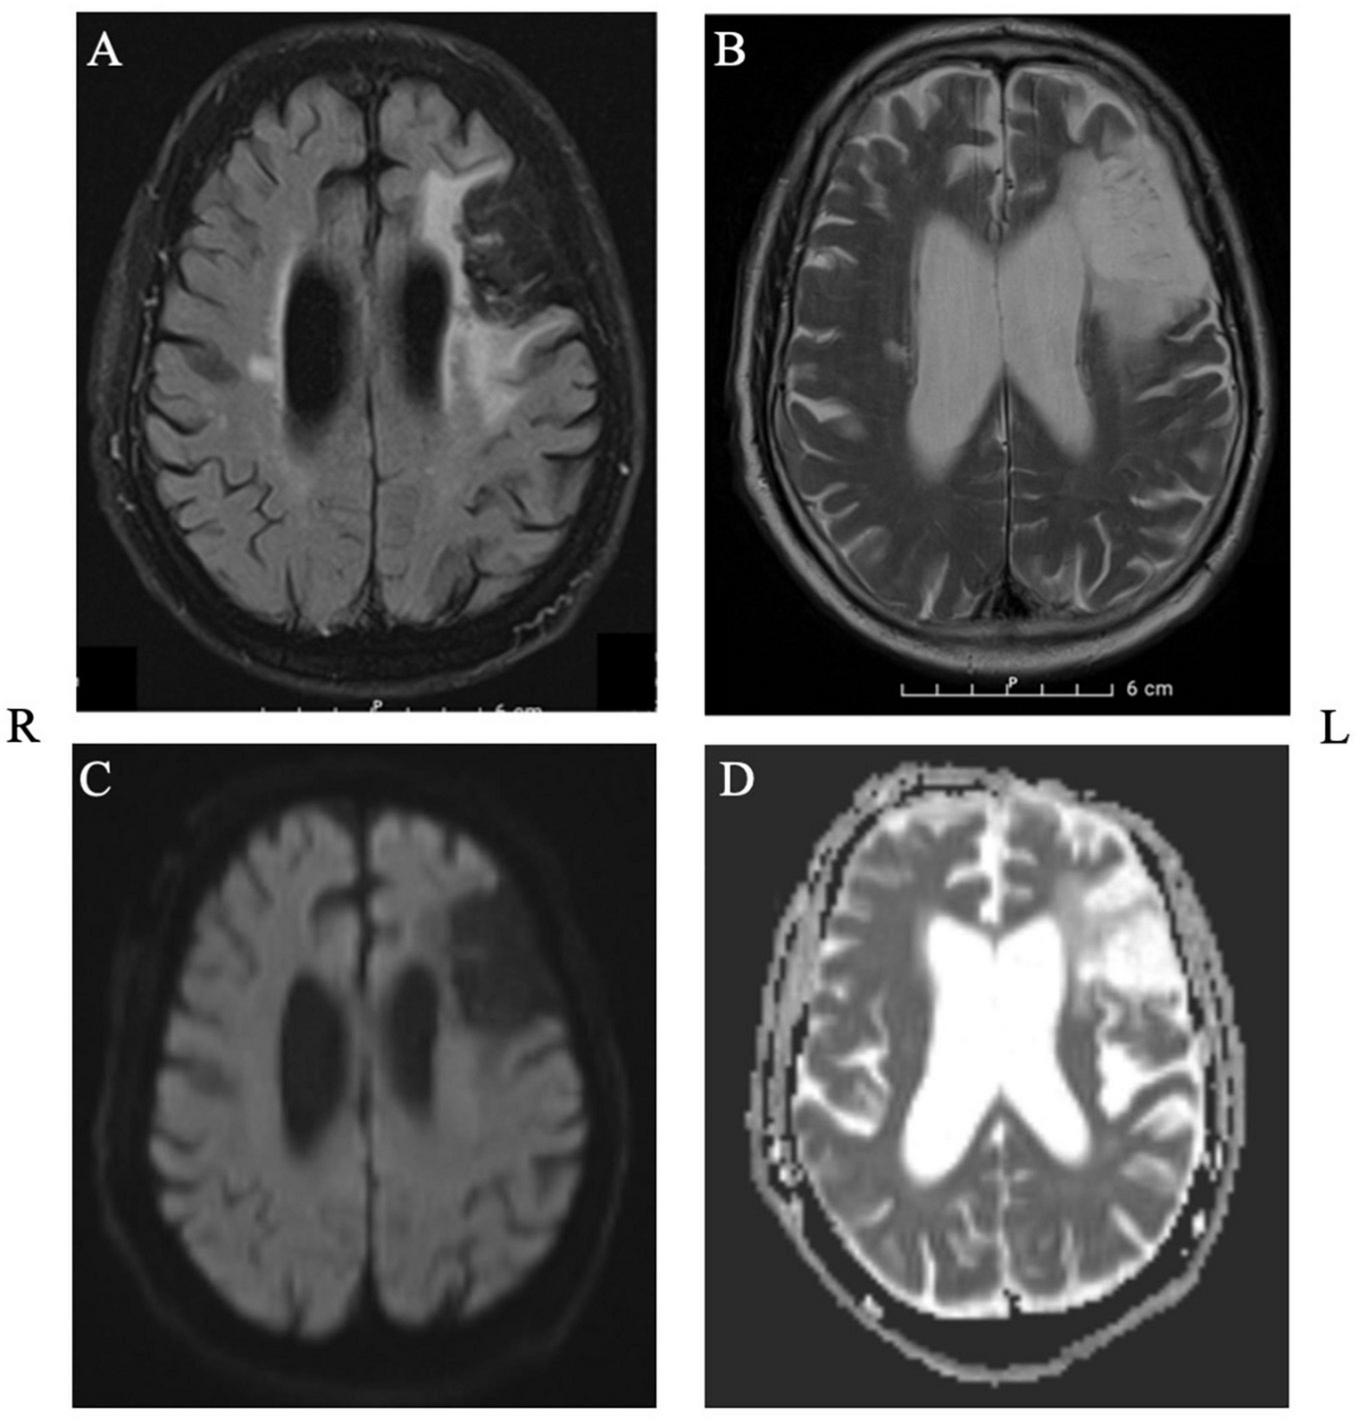

Mr. J was a 72-year-old right-handed man who suffered from left frontal ischemia (inferior and middle frontal gyrus, until pars opercularis), consistent with an infarct of the left middle cerebral artery (MCA), 3 years prior to our current study. He presented to the emergencies with expressive aphasia and a paresis of the facial nerve. The MRI revealed a major peripheral chronic left frontal media infarction and a chronic cortico-subcortical infarction at the level of the precentral gyrus on the right (Figure 1). Aside from aphasia, the neurological examination at the time of intervention indicated normal awareness, normal force distribution, intact sensitivity and good coordination and reflexes.

FIGURE 1

Structural MRI depicting the extent of the lesion in axial plane. Panel (A): T2_FLAIR, Panel (B): T2_TSE, Panel (C): DWI, Panel (D): ADC.